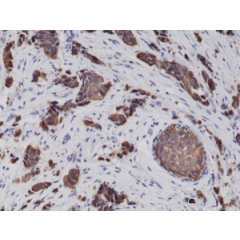

anti-Cytokeratin-17 (human), Rabbit Monoclonal (RM351)

anti-Cytokeratin-17 (human), Rabbit Monoclonal (RM351)

REV-31-1237-00 REV-31-1237-00-R100 100 µl CHF 468.00